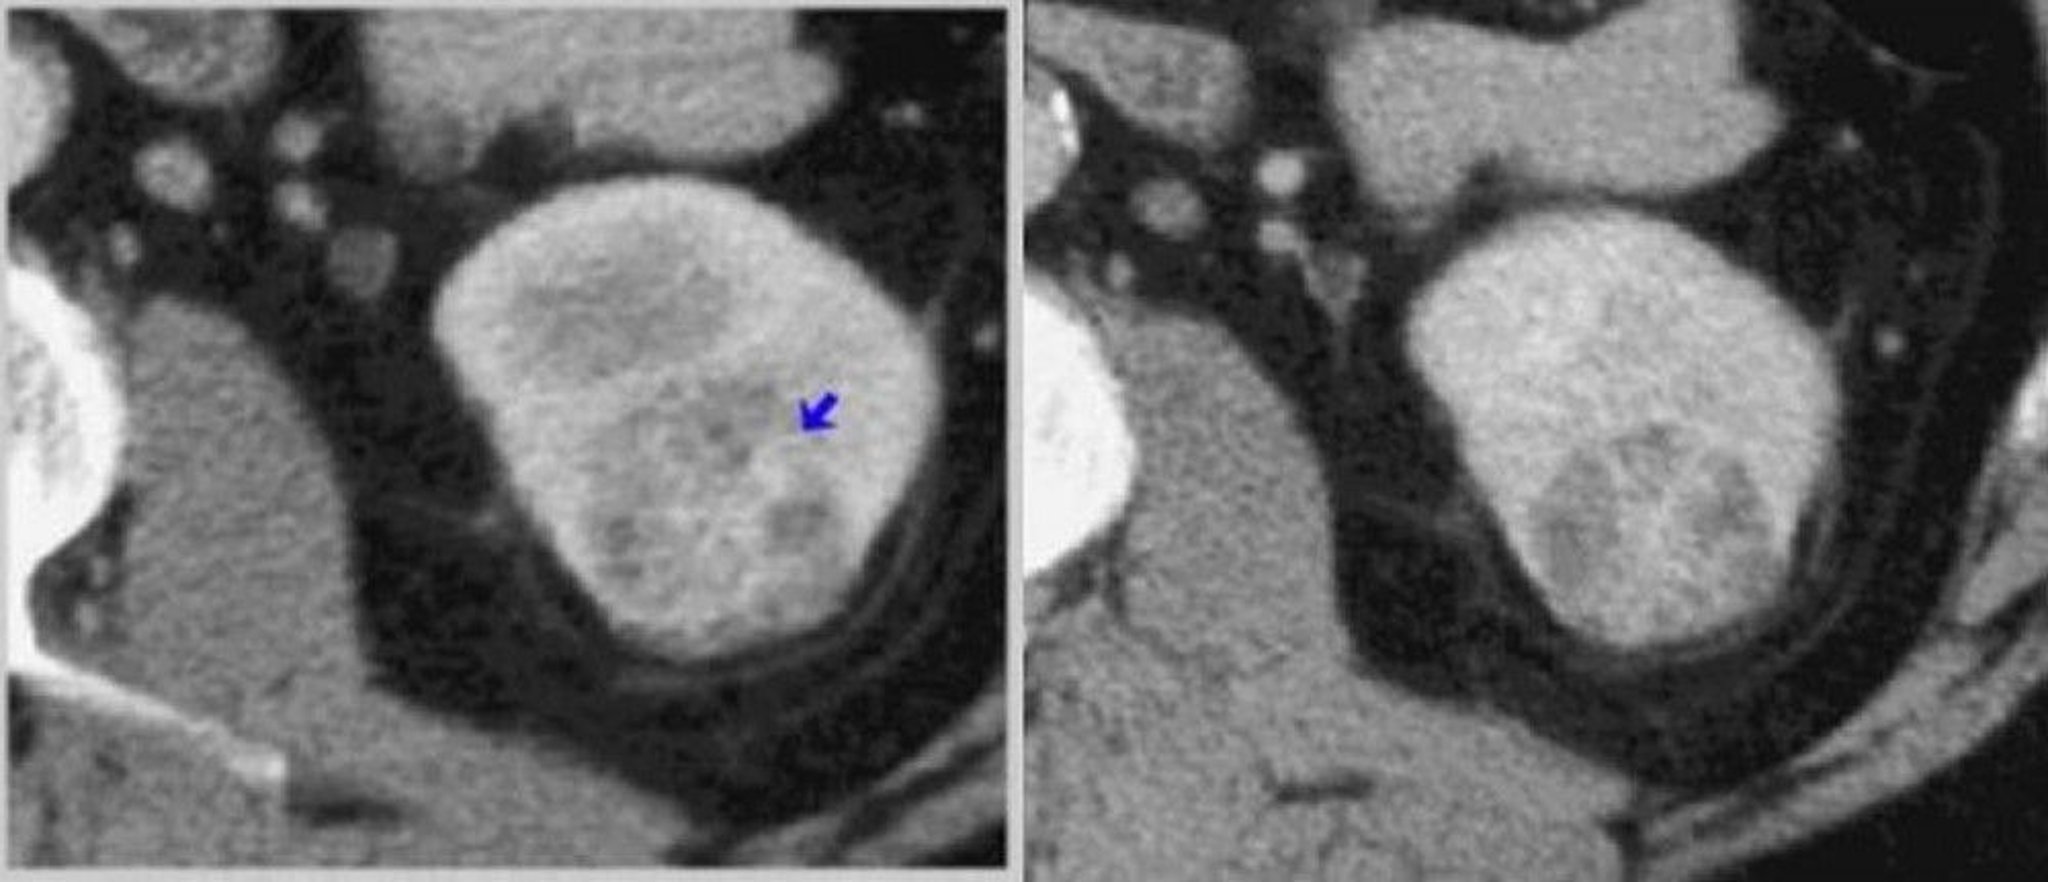

Chụp CT thận có thuốc cản quang (pha tủy vỏ và pha sinh thận)

Ở bên trái, chụp CT pha vỏ não cho thấy một khối u ngấm thuốc không đồng nhất (mũi tên). Ở bên phải, chụp CT pha thận xác định khối u rõ hơn.